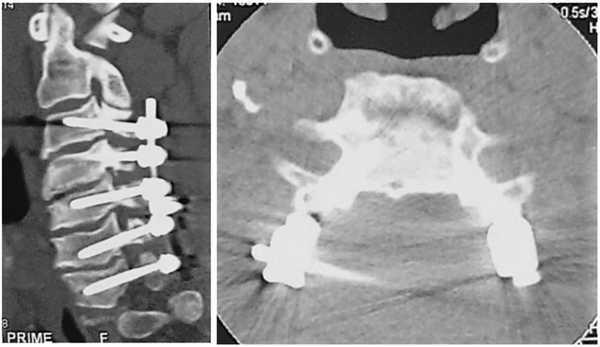

Выполнена операция: дискэктомия СIII—СIV, СIV—СV, СV—СVI, СVI—СVII, корпорэктомия СV, СVI, удаление оссифицированной задней продольной связки, оссифицированных грыж дисков, декомпрессия спинного мозга и корешков на уровне СIV—СVI, коррекция деформации позвоночника, корпородез СIII—СIV кейджем, СIV—СVI — меш-кейджем с фиксацией пластиной (рис. 3). Рис. 3. МСКТ-контроль (сагиттальная, коронарная, аксиальная проекции).

Выполнена операция: транспедикулярная фиксация СIII—СIV—СV—СVI—СVII, ламинэктомия СIV, СV, СVI, резекция дужек СIII—СVII, фораминэктомия СIII—СIV—СV—СVI с обеих сторон, декомпрессия спинного мозга и корешков на уровне СV—СVI (рис. 7). Рис. 7. МСКТ-контроль (сагиттальная и аксиальная проекции).